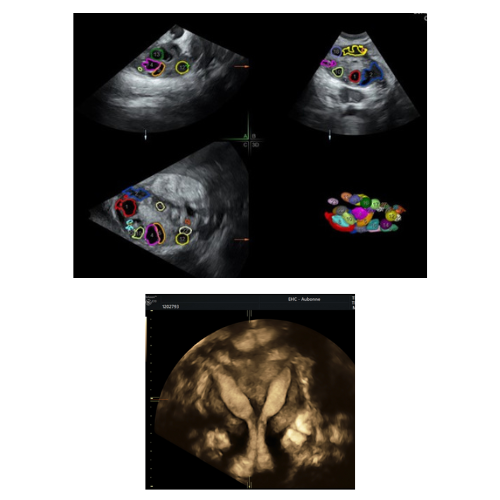

Hôpital d'Aubonne